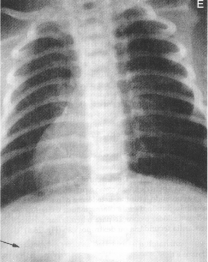

Fig. 26.7. Radiografia ântero-posterior do tórax em um paciente com situs inversus atrial e visceral, bem como com as grandes artérias normalmente relacionadas. A sombra hepática é localizada no quadrante superior esquerdo do abdômen, e a câmara de ar do estômago borbulhante (seta) situa-se à direita. Há dextrocardia com o eixo cardíaco base-ápice apontado à direita, e o tamanho e o formato do coração são normais. E, esquerda.